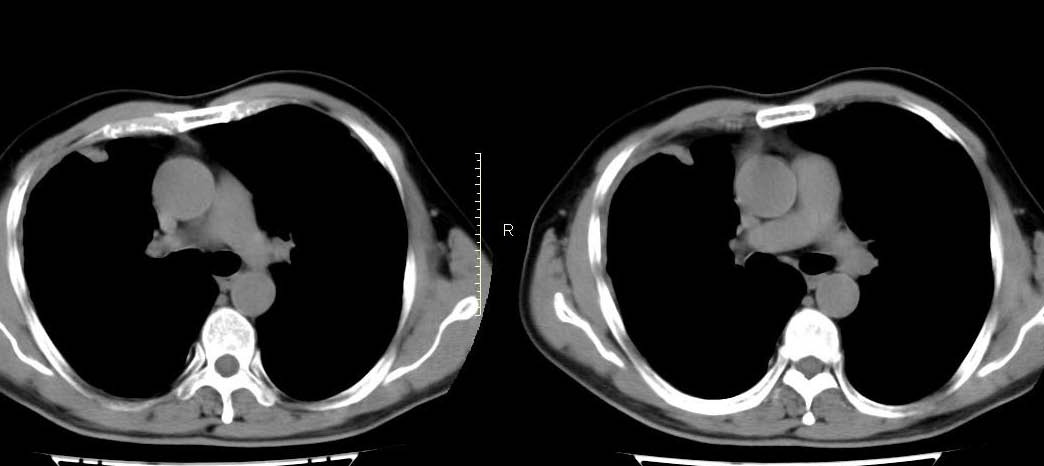

男,56岁,右侧腋窝下巨大软组织包块转移。欢迎讨论。

该病例为已经确诊的右侧恶性胸膜间皮瘤病例,有青石棉接触史,早期就是胸水,右侧胸壁“花边状改变”,心隔角区软组织阴影形成。近期右侧腋窝下巨大软组织包块,病检为转移瘤。图片没有完全考来,主要是给大家看一下胸膜间皮瘤的病例。,右侧

1)右肺中叶节段性肺不张。2)右肺中叶肺癌不排除。3)右侧胸膜增厚。

右心膈角区一不规则肿块伴相邻胸膜不规则增厚,考虑胸膜间皮瘤(恶性)?右肺中叶内侧段肺癌?建议穿刺活检。